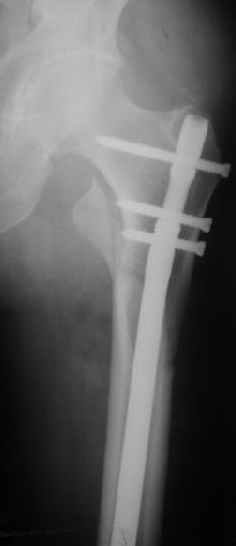

При межвертельных переломах с цефаломедуллярными гвоздями бывает, что проксимальый винт проходит или черед периферический отломок, или прямо над ним. И если остался диастаз, то этот винт при осевой нагрузке не дает сблизиться отломкам. Пример такого остеосинтеза в застарелом случае в приложении.

В качестве предупреждающей меры можно долотом разрушить латеральную стенку дистального отломка под винтом.